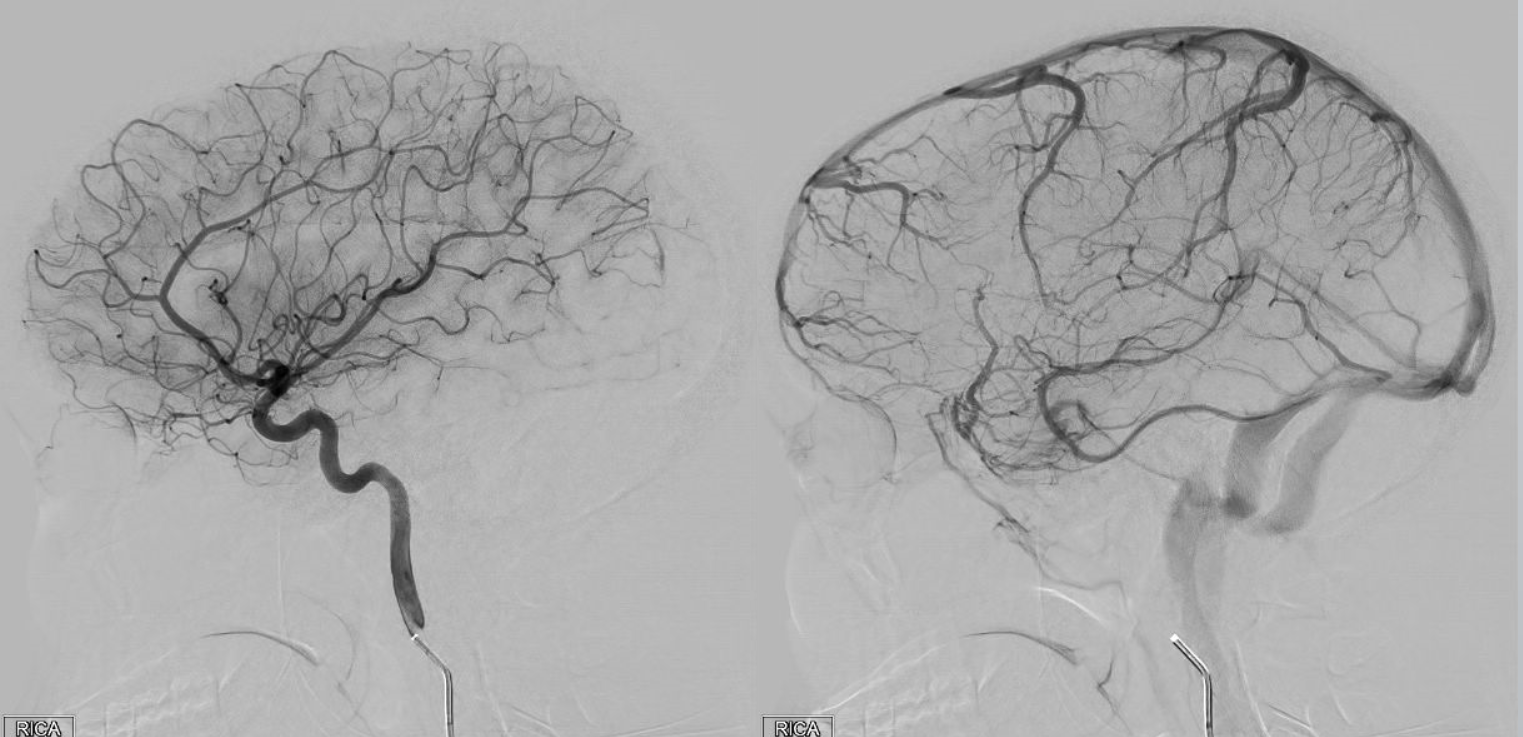

Хирургические процессы при эмболизации гемангиомы на фото

Раздел: Снимки-откровения